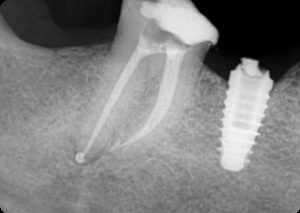

Perioseal

External interface

Tapered body

Implant threadsThread typeThreadedV-shaped threads

Apex shapeApical groovesCollarCurved apexFlangeWider flange